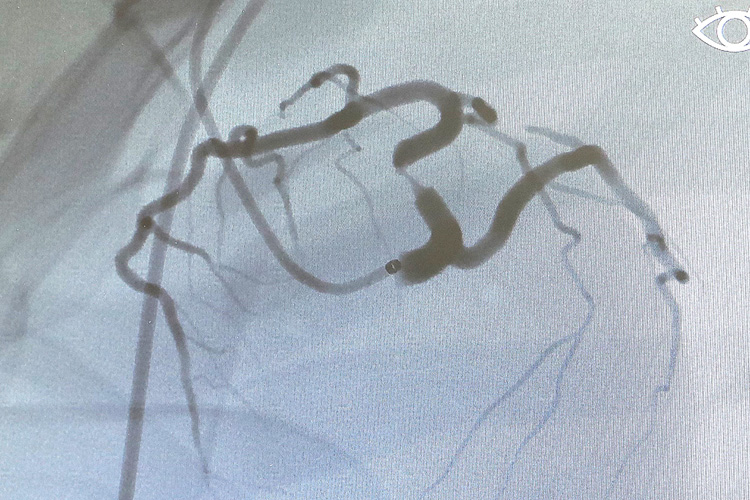

- あなたも名医!狭心症の治療を体験してみよう!(循環器内科)